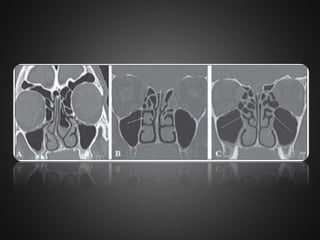

 Sphenoethmoid cell(Onodi cell) :  This is formed by lateral and posterior pneumatization of the most posterior ethmoid cells over the sphenoid sinus.  The presence of Onodi cells increases the chance that the optic nerve and / or carotid artery would be exposed in the pneumatized cell.

 A,b)bilateral onodicells.  C)sphenoid sinus ostium without connection with the Onodi cell.